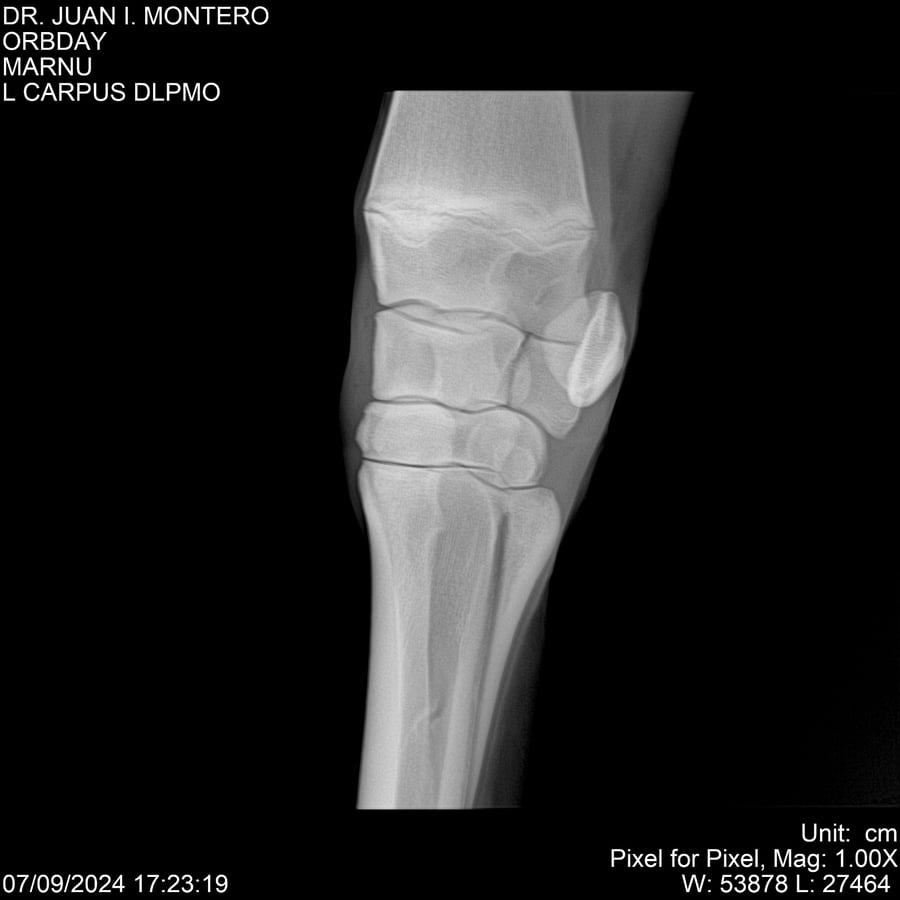

• Empresa: Abelenda N. R., Walter Hugo